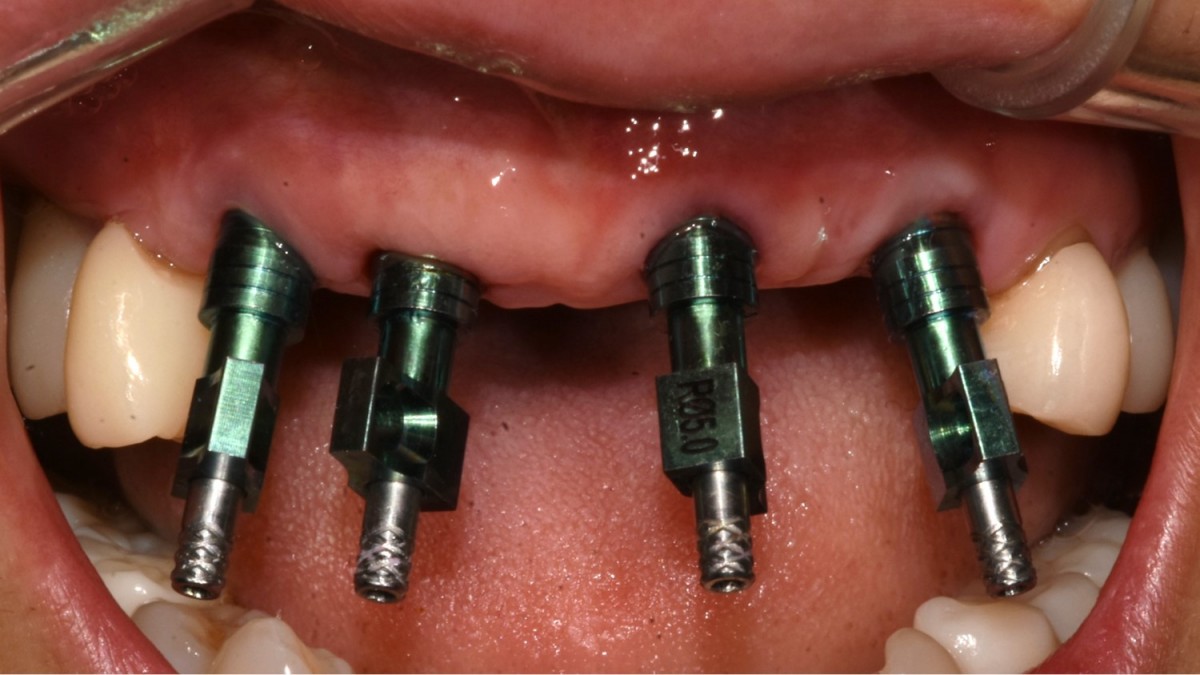

▲Fixture to be placed. Arum® implant NB1

▲Implant placement GBR